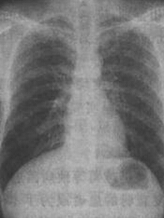

兩肺中下野見斑片狀陰影

4、x線檢查表現(xiàn)為兩肺紋理增粗,或兩肺中下野見斑片狀陰影。或小片狀陰影融合成大片狀陰影,可合并大片肺不張。